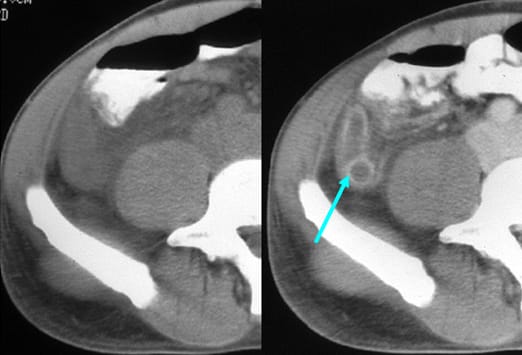

Intravenöses Kontrastmittel (siehe Abbildung) ist ein wichtiges diagnostisches Hilfsmittel. Dieser Patient präsentierte sich mit einer Hypotonie und einer gram-negativen Sepsis, allerdings ohne abdominelle Schmerzen in der klinischen Untersuchung. Das Bild auf der linken Seite, welches mit oralem, aber ohne intravenöses Kontrastmittel durchgeführt wurde, ergab keinen schlüssigen Befund. Das Bild auf der rechen Seite zeigt die erneute Untersuchung nach Gabe von intravenösem Kontrastmittel. Dieses stellt eine verdickte, vermehrt kontrastierte Appendixwand und entzündliche Veränderungen des umgebenden Fettgewebes dar.